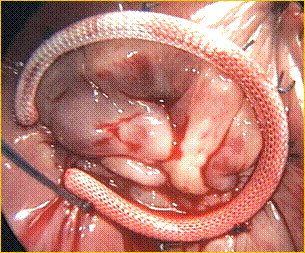

STENOSI MITRALICA CON TROMBOSI MASSIVA DELLfATRIO SINISTRO

Nellfadulto normale la superficie dellfostio valvolare è di circa 4-6 cm². Quando la superficie valvolare si riduce a meno di 2 cm², il passaggio di sangue in diastole dallfatrio sinistro al ventricolo sinistro può essere mantenuto solo aumentando la pressione a livello dellfatrio sinistro; si genera cioè un aumento del gradiente diastolico transmitralico che è la caratteristica fondamentale della stenosi mitralica. Il sovraccarico di pressione nellfatrio sinistro comporta una progressiva dilatazione di questa cavità, che può raggiungere notevoli dimensioni, e determinare lfinsorgenza di fibrillazione atriale che a sua volta, determinando una stasi ematica nellfatrio sinistro, favorisce la formazione di trombi allfinterno della cavità atriale. La trombosi, sia valvolare che atriale, è responsabile delle frequenti embolie sistemiche, talora anche fatali, che fanno parte del quadro clinico della valvulopatia mitralica ( una curiosità anatomo - patologica è rappresentata dai cosidetti trombi ga pallah , conseguenti al distacco di masse trombotiche dalle pareti striali, che possono fluttuare liberamente nella cavità atriale ). Col passare del tempo si può osservare una deposizione calcifica ga guscioh sulla massa trombotica rotondeggiante. Le ripercussioni sul letto vascolare polmonare sono costanti in questa valvulopatia e sono costituite dalla dilatazione delle vene polmonari, espressione anatomica dellf ipertensione polmonare.